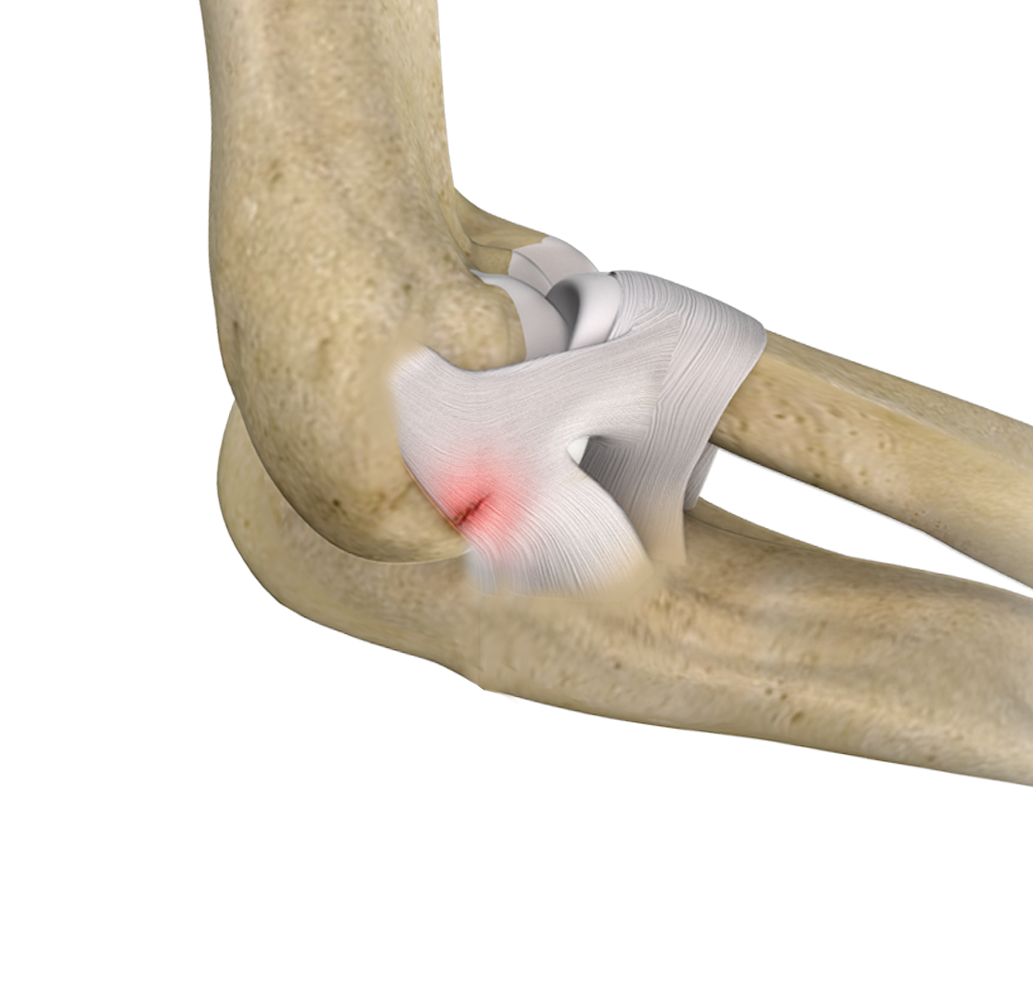

Ulnar Collateral Ligament (UCL) Injury

The ulnar collateral ligament (UCL), also called the medial collateral ligament, is located on the inside of the elbow and connects the ulna bone to the humerus bone.

Elbow Ligament Injuries

Elbow ligament injuries are injuries to the tough elastic tissues that connect the bones of the elbow joint to each other.

Lateral Ulnar Collateral Ligament Injuries (Elbow)

A ligament is a band of elastic, tough fibrous connective tissue around a joint.

Elbow Tendon and Ligament Repair

The elbow joint is supported by the ulnar collateral ligament, radial collateral ligament, and the annular ligament.